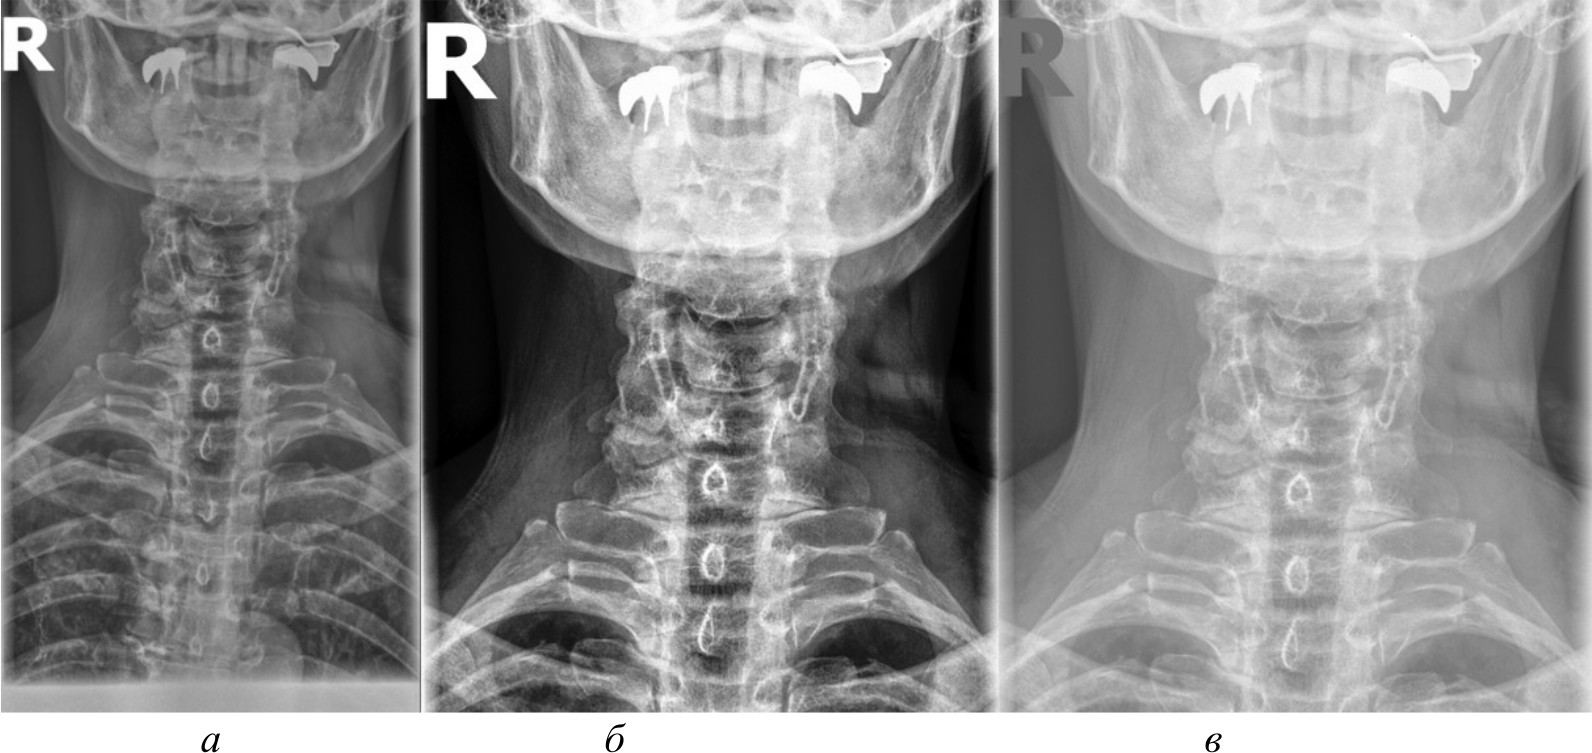

Рис. 2. Изображение, полученное при помощи специализированного программного обеспечения (а), метод базового отображения в Python (б), метод базового отображения Python с применением медианного фильтра (в)

Исходя из полученных изображений при использовании различных методов можно сделать следующие выводы:

- базовое отображение DICOM-данных с помощью библиотеки Pillow показало наличие значительного количества шумов и размытых объектов на полученных изображениях, что затрудняет четкое обнаружение анатомических ориентиров;

- применение медианного фильтра для сглаживания артефактов привело к чрезмерному размытию деталей на изображениях, сделав их еще менее пригодными для дальнейшего анализа;

- использование методов эквализации гистограммы продемонстрировало значительное улучшение контрастности и четкости визуализации анатомических структур по сравнению с базовым отображением и медианной фильтрацией;

- гамма-коррекция изображений, в отличие от эквализации, больше повлияла на яркость, нежели на контрастность, поэтому показала себя хуже в контексте задачи выделения ключевых анатомических ориентиров;

- отображение изображений в формате PNG, полученных из исходных DICOM-данных после применения ряда предварительных обработок с помощью специализированного программного обеспечения, продемонстрировало качество визуализации несколько меньшее, чем у методов эквализации, но при этом превосходящее качество других рассматриваемых методов обработки. В итоге комплекс предварительных обработок, необходимых для конвертации DICOM-данных в формат PNG, позволяет достичь качества визуализации, которое хотя и уступает эквализации, но превосходит другие методы.

Рис. 3. Метод адаптивной эквализации гистограммы, метод стандартной эквализации гистограммы, метод гамма-коррекции